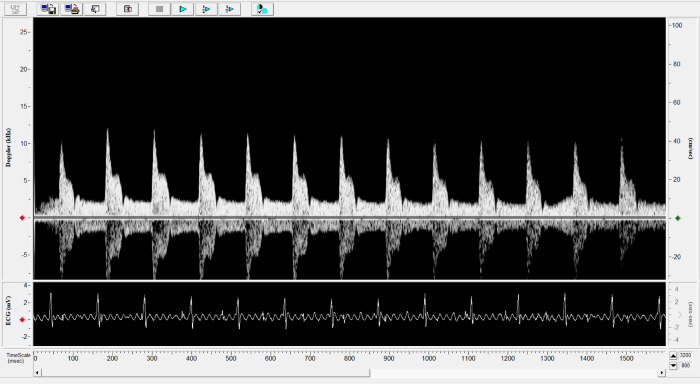

Imaging gallery - Doppler Flow Velocity System

Pulmonary Flow. Image Credit: Scintica Instrumentation Inc.